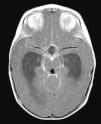

Radiología Solución del caso 30. Papiloma de los plexos coroideos con realce meníngeo

Solución del caso 30. Papiloma de los plexos coroideos con realce meníngeo

Solution to case 30. Choroid plexus papilloma with meningeal enhancement